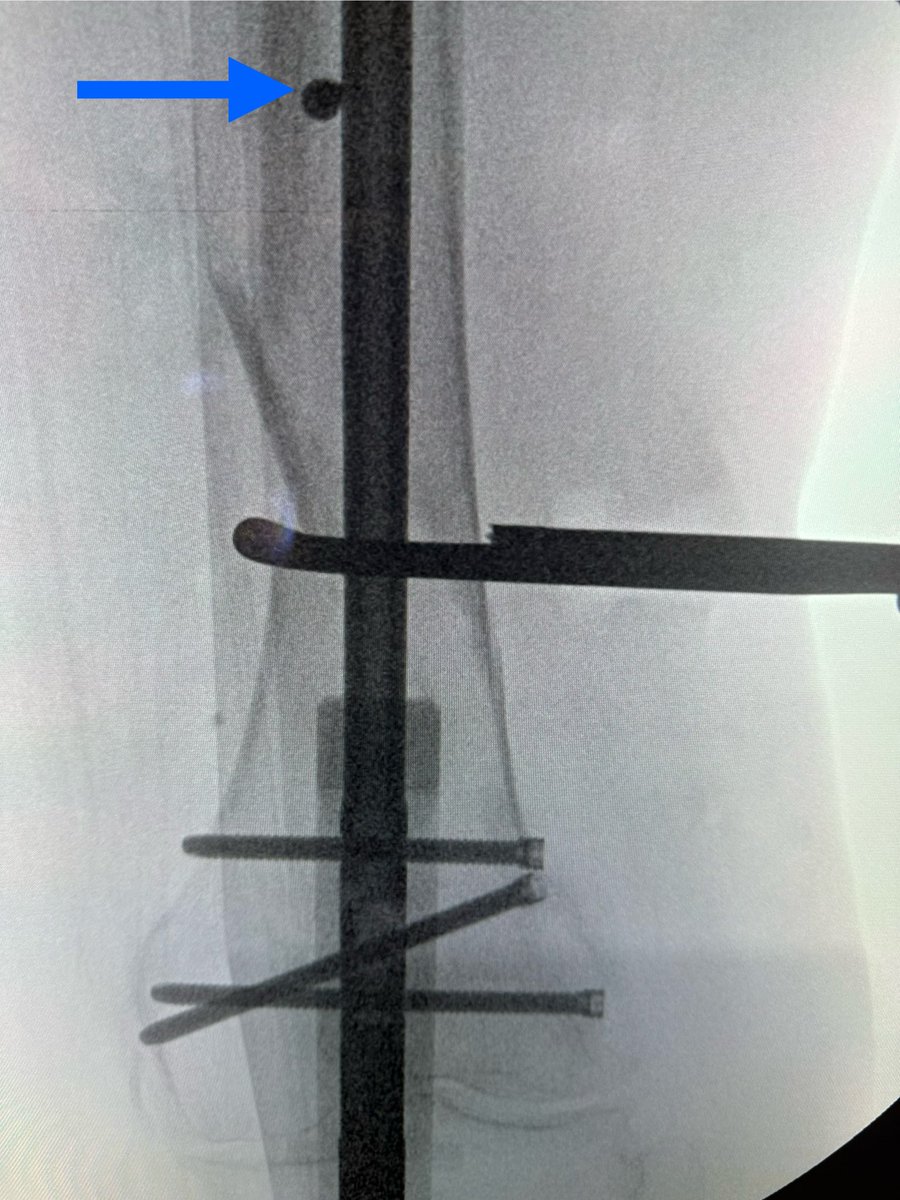

My example of how bell clapper screws help prevent translation deformity. Fracture aligned with clamp but when released it coronally translated (red). Reclamped & used bell clapper screw (blue) that narrowed proximal canal, allowing no more shift. Paper: pubmed.ncbi.nlm.nih.gov/30086037/